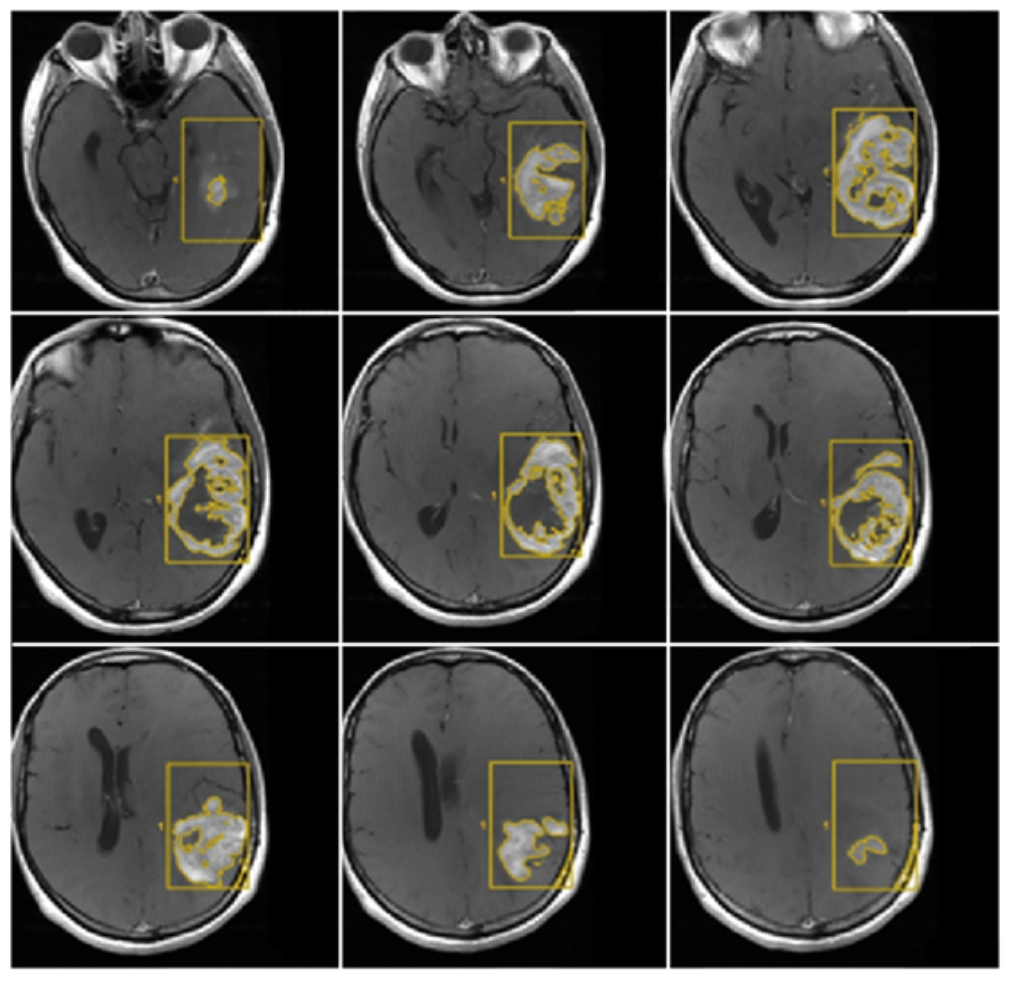

- Morphological appearance: We divided GB lesions into three categories based on the enhancing wall thickness: thin, <3 mm; thin-nodular, when the enhancing wall showed focal thickenings > 3 mm; and nodular, when solid appearance was predominant and intratumoral necrosis was absent or <1.5 cm3. A total of 11 (13%) masses showed a thin pattern, 51 (58%) showed a thin-nodular pattern, and 25 (29%) showed a nodular pattern.